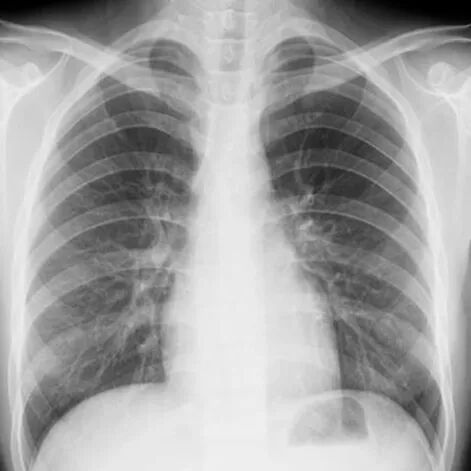

DR检查

优点是价格便宜、速度快、辐射剂量小。是肺部及全身骨骼检查的第一选择。比如平时有个感冒咳嗽想拍个片子看看有没有肺炎、跌打损伤看看骨头有没有明显的骨折等,首选DR检查。它的缺点是图像重叠,诊断精确性不高。当遇到诊断不明确的时候,需要进一步行CT或MR检查。